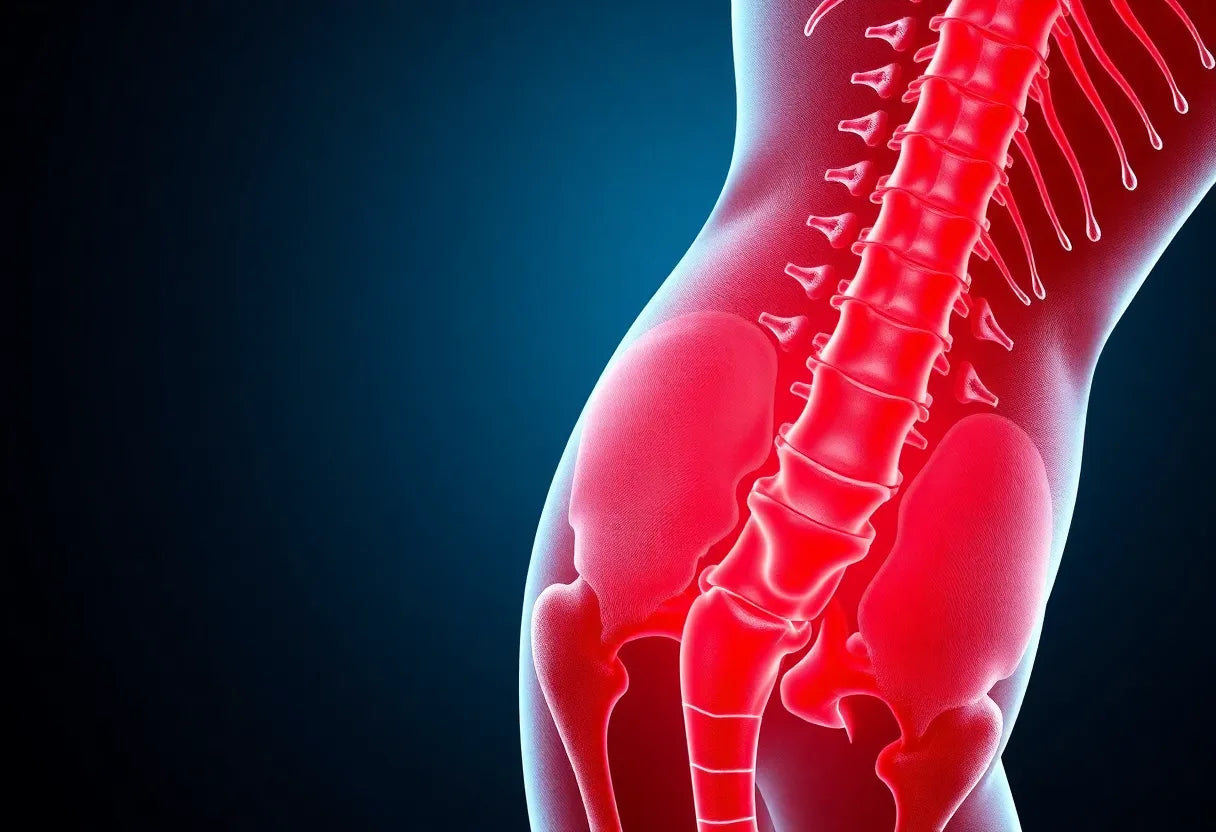

Rug- en beenpijn kunnen je dagelijkse leven aanzienlijk beïnvloeden, vooral wanneer deze symptomen worden veroorzaakt door een hernia. Een hernia, ook wel bekend als een tussenwervelschijfuitpuiling, is een aandoening waarbij de zachte kern van een tussenwervelschijf door een scheur in de buitenste laag naar buiten drukt. Dit kan druk uitoefenen op nabijgelegen zenuwen, wat resulteert in pijn die vaak uitstraalt van de rug naar het been. Het begrijpen van de symptomen en het mechanisme van een hernia is cruciaal voor het effectief beheren van deze klachten.

Rug- en beenpijn kunnen je dagelijkse leven aanzienlijk beïnvloeden, vooral wanneer deze symptomen worden veroorzaakt door een hernia. Een hernia, ook wel bekend als een tussenwervelschijfuitpuiling, is een aandoening waarbij de zachte kern van een tussenwervelschijf door een scheur in de buitenste laag naar buiten drukt. Dit kan druk uitoefenen op nabijgelegen zenuwen, wat resulteert in pijn die vaak uitstraalt van de rug naar het been. Het begrijpen van de symptomen en het mechanisme van een hernia is cruciaal voor het effectief beheren van deze klachten.

Een hernia in de onderrug manifesteert zich meestal door een combinatie van rugpijn en beenpijn, die vaak ernstiger kan zijn dan de rugpijn zelf. Dit komt doordat de hernia de zenuwen kan irriteren die naar het been lopen, wat leidt tot uitstralende pijn, tintelingen, gevoelloosheid en soms zelfs krachtverlies in het been. Deze symptomen kunnen variëren in intensiteit en kunnen verergeren bij activiteiten die druk op de wervelkolom verhogen, zoals hoesten, niezen of langdurig zitten.

Een hernia ontstaat wanneer de zachte kern van een tussenwervelschijf door een scheur in de buitenste laag naar buiten puilt, wat druk kan uitoefenen op de nabijgelegen zenuwen. Dit mechanisme is verantwoordelijk voor de intense pijn die vaak geassocieerd wordt met deze aandoening. Wanneer de zenuwen die van de rug naar het been lopen, zoals de nervus ischiadicus, worden geïrriteerd, kan dit leiden tot uitstralende pijn en andere symptomen in het been. Deze pijn is vaak ernstiger dan de rugpijn zelf en kan gepaard gaan met tintelingen, gevoelloosheid en zelfs krachtverlies.